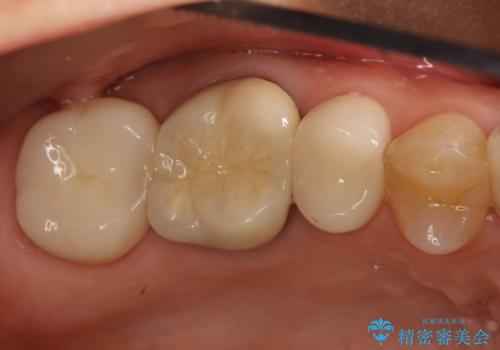

適合が悪いかぶせ物と詰め物の再治療

虫歯もしっかり除去して、適合の良い補綴物を装着しました。